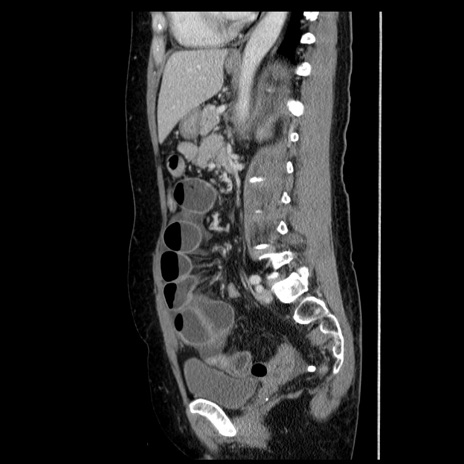

症例6(矢状断像)

【症例】50歳代女性

【主訴】下腹部痛

【現病歴】本日朝より下痢2回あり。 昼食を食べた後、嘔吐3回、下腹部痛認め、症状軽快せず、当院救急搬送。

最終食事:本日昼(生ものなし)。 昨日の夜、刺身を食ぺたとのこと。周囲に同様の症状の者なし。普段、排便は毎日あるとのこと。

【既往歴】卵巣癌術後(8年前に当院で卵巣摘出)

【身体所見】 意識清明、腹部:平坦、腸蠕動音→、やや硬、下腹部自発痛・圧痛あり、反跳痛あり、筋性防御なし。

【データ】WBC 16000、CRP 0.01